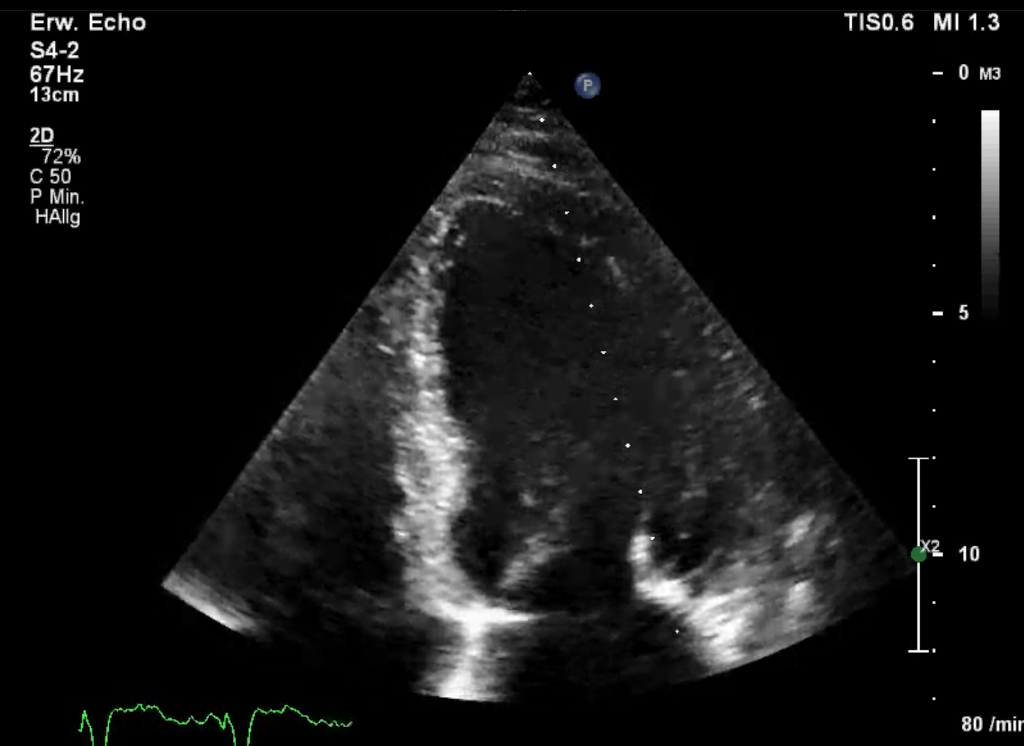

2D-Bild

M-Mode

2D-Bild (realtime)